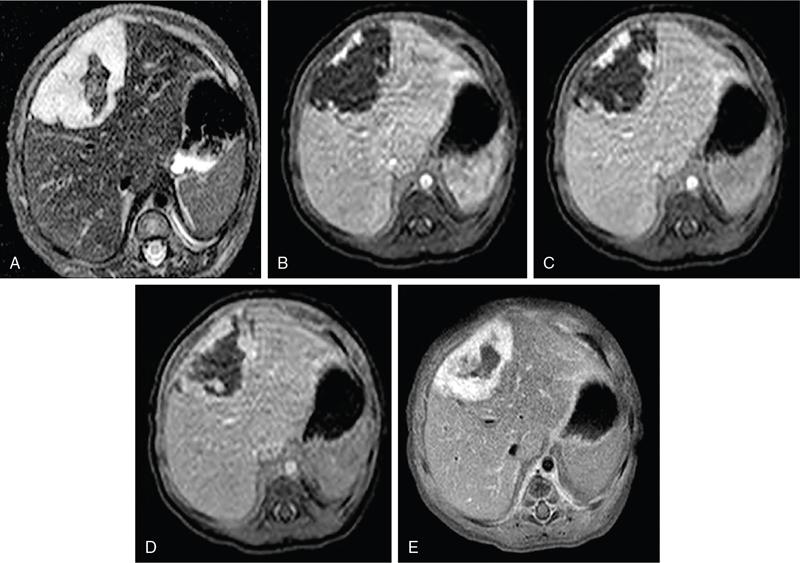

DIFFUSE PARENCHYMAL DISEASES OF THE LIVER Ishan Kumar, Ashish Verma The hepatic parenchyma is the site for multiple essential, interrelated, and complex metabolic activities to assimilate nutrients, detoxify the body, and synthesize vital molecules such as enzymes, hormones, cofactors and essential components of the coagulation pathway. The chemical reactions involved in each of these activities pose a threat to the hepatocytes, which may be damaged leading to the initiation of reparative processes. Further, the liver, being a highly vascular organ with multiple metabolic activities, is liable to be involved in many systemic vascular and metabolic disorders. On one hand, such changes cause healing of the tissue injury, but on the other hand, lead to diffuse parenchymal changes, which may result in suboptimal functioning of the organ. Such a condition is labelled as ‘diffuse liver disease’ and includes (a) diseases caused due to storage of certain chemical products of such chemical reactions labelled as ‘storage disorders’, (b) diseases caused due to reduction of blood flow to the organ, (c) parenchymal injury due to stasis of bile at various levels in the pathway due to varied causes, and (d) involvement of liver in systemic or organ-based inflammatory disorders. The mainstay of diagnosis of diffuse liver diseases is the detection of alterations in the biochemical parameters in blood indicative of liver function, which however is nonspecific to various aetiologies. The diffuse liver diseases in children are quite different from those in the adult population and constitute mainly of congenital or inherited metabolic and vascular diseases as opposed to diseases of acquired aetiologies in the latter population. The gross and microscopic pathological changes are accordingly different in the paediatric population and may be utilized to add specificity to the biochemical indicators as far as aetiological diagnosis is concerned. The invasive and potentially hazardous sampling mandated for histological evaluation of liver parenchyma has been replaced by an array of imaging modalities in recent times. The present chapter presents a review of the currently available imaging modalities (viz. cross-sectional imaging modalities such as ultrasonography, computed tomography [CT] and magnetic resonance [MR] imaging) for evaluation of diffuse liver diseases along with the pertinent imaging features and guidelines for their rational use in various indications. Also a short review of certain key technical and technological details is included. Jaundice and hepatomegaly are the most common clinical manifestations of liver disease. Anorexia is a nonspecific sign, often present in acute or chronic liver disease. Jaundice is a sign of increased bilirubin content in the blood, that can exist in four forms: (i) unconjugated bilirubin bound to albumin, (ii) unbound unconjugated bilirubin, (iii) conjugated bilirubin and (iv) δ fraction. Direct fraction includes both conjugated bilirubin and δ bilirubin. Conjugated hyperbilirubinemia is due to decreased excretion by liver or biliary tract obstruction. Pruritus, spider angioma on face and neck, ascites, portal hypertension, botchy palmer erythema, subcutaneous xanthoma, gastrointestinal (GI) variceal bleed, encephalopathy, renal dysfunction and pulmonary involvement are manifestations of advanced cirrhosis. Evaluation of total serum bilirubin and its fractional analysis into indirect (unconjugated) and direct (conjugated and δ fraction) bilirubin helps to distinguish between elevation caused by haemolysis and that due to hepatic dysfunction or biliary obstruction. Elevations in alkaline phosphatase (ALP), 5′ nucleotidase, and γ-glutamyl transpeptidase (GGT) levels are an indicator of biliary obstruction. However, it should be noted that normal growing children have significant elevations of serum ALP activity. AST (aspartate aminotransferase) and ALT (alanine aminotransferase) are significantly raised in acute hepatitis. ALT rise disproportionate to AST rise is seen in viral hepatitis. A predominant rise in AST is seen in echovirus infection, various metabolic diseases or alcohol-induced hepatitis. These aminotransferases are also elevated in NAFLD/NASH. ALT/AST rise is less marked in chronic liver disease. PT-INR, serum albumin levels can evaluate the hepatic synthesis function. Hypoalbuminemia suggests a bad prognosis. γ-Globulin is elevated in autoimmune hepatitis (AIH). Alpha-fetoprotein is raised in hereditary tyrosinemia or hepatic neoplasms. Indications of liver biopsy in the paediatric age group include neonatal cholestasis, metabolic liver disease, NAFLD, congenital hepatic fibrosis, abnormal biochemical liver tests of unknown aetiology, intestinal failure associated liver disease, acute liver failure and liver tumours. Although biopsy of children and infants is considered a safe procedure, due to incidences of shock, the North American Society for Pediatric Gastroenterology and Nutrition (NASPGHAN) has recommended liver biopsy in children not to be necessarily performed as outpatient procedures. Sonography-guided percutaneous liver biopsy has been reported to be safer, more efficient, more comfortable and only marginally more expensive than blind biopsy. The use of coaxial technique, determination of the number of passes and use of track embolization were at the discretion of the interventional radiologists. In cases of uncorrected PT-INR elevation, transjugular liver biopsy can be performed. Ultrasound (US) is a valuable tool in the diagnosis and management of diffuse liver diseases. It provides useful information about the size, surface, parenchymal architecture, biliary channels and blood flow of the liver. US examination of the liver is performed in the supine position with a convex (5–7.5 MHz) probe. High-frequency (7.5–12 MHz) linear transducers can be used in young infants because of their small size. US examination can be completed with the colour Doppler technique and US elastography, if needed. CT protocol typically requires image acquisition during the multiple phases with a slice thickness of 5 mm or less and a pitch ranging from 1 to 1.5. Contrast injected is 2 mL/kg through manual or mechanical injection. The arterial phase begins at 10–15 seconds and the portal phase is at 20–40 seconds after contrast injection. Equilibrium phase is obtained at 3 minutes, when needed. MRI protocol to evaluate paediatric liver chiefly includes free-breathing sequences, due to the challenge offered by an inadequate breath-hold in these patients. Due to the same reason, motion insensitive single-shot HASTE sequences or motion insensitive T1-weighted spoiled GRE single-shot sequences are also widely utilized in paediatric MR examinations. In slightly older children with a relatively uniform breathing pattern, external trigger signals from a breathing belt, or navigator techniques may be used to overcome motion artefacts from breathing. T1- and T2-weighted turbo spin-echo (TSE) sequences and T2-weighted single-shot sequences in axial and coronal planes are initially acquired to evaluate the anatomy and screen for pathologies. This is followed by a gradient echo (GRE) images to examine vascular structures. Multiecho images with T1-weighting can be acquired to evaluate the fat content of lesions. Contrast-enhanced MRI with intravenous injection of gadolinium (Gd)-based contrast agent is performed as routine in cases with suspected portal hypertension or in any associated suspected neoplastic lesion. This is usually clubbed with MRA for vascular mapping. Arterial phase and portal phase should be acquired 10–15 seconds and 20–30 seconds, respectively after the start of contrast agent injection. GRE T1-weighted sequence should be repeated continuously four or five times to include achieve all phases of liver perfusion. Finally, steady-state imaging should be performed in the equilibrium phase (3 minutes) using T1-weighted and T1-weighted fat-suppressed imaging sequences. MRI contrast media should be administered with caution after evaluation of eGFR, and is safer than the iodinated contrast media needed for CT scan examination, and is hence preferred. Liver size measurement is commonly obtained in one of the two ways (a) an anterior to the posterior measurement of the liver in the midclavicular line, (b) a dome-to-tip longitudinal measurement of the liver in the midclavicular line. Table 9.8.1.1 provides suggested upper limit values of liver and spleen length for various paediatric age groups. Despite advances in 3D US, volume measurements of liver size have not been incorporated in the routine clinical practice because it is time-consuming, requires considerable skill and technically difficult fusion of multiple 3D sweeps. Nonalcoholic fatty liver disease (NAFLD) is referred to as triglyceride accumulation in hepatocytes and encompasses a broad range of clinicopathological entities ranging from simple steatosis, steatohepatitis to cirrhosis. Its worldwide reported prevalence is approximately 2.6%–10% in the general paediatric population and as high as 38% of obese children under the age of 19 years. In India, the reported prevalence is as high as up to 22% in the general paediatric population and up to 45% in obese and overweight children. Hepatic steatosis currently is the most common cause of chronic liver disease in paediatric patients. Table 9.8.1.2 highlights the causes of hepatic steatosis in paediatric age group. The pattern of injury is similar to alcoholic liver disease. Nonalcoholic steatohepatitis (NASH) constitutes a subset of NAFLD, ranging from simple steatosis to inflammation and fibrosis. NASH in children has two distinct histological subtypes. Type 1 NASH resembles adult subtype with macrovesicular steatosis, lobular inflammation, and ballooning degeneration and perisinusoidal fibrosis. Type 2 NASH shows steatosis with portal fibrosis and is present in younger children with increased severity of obesity. ALT can be normal in 20% of the patient with NAFLD and liver biopsy is the gold standard for diagnosis as well as a semiquantitative assessment of disease severity. In clinical practice, the diagnosis and monitoring of NAFLD largely rely on ultrasonography. Grade I fatty liver refers to diffusely hyperechoic parenchyma with a well-visualized diaphragm (Fig 9.8.1). Bright liver with loss of periportal echogenicity and indistinctly visualized vessels is referred to as grade II and blurring of the diaphragm is classified as grade III fatty liver. Limitations of the US are lack of objective quantification and diminished sensitivity in cases where biopsy-proven steatosis ratio is less than 30%. Moreover, hepatic fibrosis and inflammation in cases of NASH are sonographically indistinguishable from simple steatosis. Contrast-enhanced US can diagnose the presence of fibrosis in NAFLD, which is evident from the decreased accumulation of microbubbles in the liver parenchyma. The distinction between hepatic steatosis and fibrosis is important clinically, as fibrosis can progress to cirrhosis if left untreated. US elastography has emerged as a promising technique to screen the children with NAFLD to look for ongoing steatohepatitis/fibrosis. Transient elastography is the most popular elastography technique which has shown excellent accuracy in the adult population with chronic hepatitis. However, its accuracy in NAFLD is significantly lower and the data of effectiveness in the paediatric population is limited. Acoustic radiation force impulse imaging (ARFI) has been shown to have a good correlation with AST/ALT ratios in obese children with NAFLD. An ARFI elastography value of >1.19 m/s predicts NASH-related hepatic changes in these patients while a value >1.75 m/s is suggestive of cirrhosis. Another study on shear-wave elastography has shown a high correlation in paediatric NAFLD patients with biopsy-proven hepatic fibrosis. A value of >5.1 kPa strongly predicts the presence of fibrosis whereas a value of >6.7 kPa is suggestive of stage ≥F2 fibrosis (Brunt scoring system). CT is a common modality utilized for assessment of hepatic pathologies, however is seldom used for assessment of NAFLD because of the risk of ionizing radiation. On noncontrast CT, liver attenuation <40 HU or hepatic attenuation 10 HU lesser than that of the spleen is considered as a sign of steatosis. Recent literature advocates the utilization of MRI in the evaluation of NAFLD. Fat imparts high signal intensity to the liver parenchyma on T1-weighted spin-echo MR images while it is mildly hyper- to hypointense on T2-weighted images. Conventional spin-echo imaging is relatively insensitive to mild-to-moderate fatty infiltration of the liver. The most commonly employed technique for detection of steatosis is chemical shift imaging (Dixon technique or dual-echo method) which utilizes two sets of gradient-echo images of the liver, that is in-phase and out-of-phase. On in-phase echo-time, water and fat signals add whereas, on out-of-phase echo-time, water and fat signals cancel each other. In nonfatty livers, the signal intensity of the liver parenchyma is unchanged between in- and opposed-phase images whereas a fatty liver shows a notable reduction of signal intensity on the opposed-phase images. Iron deposition in the liver can interfere with the assessment of steatosis. MR spectroscopy has been one of the most reliable techniques for the evaluation of hepatic steatosis (Fig 9.8.1.2). Protons in water molecules resonate at 4.7 ppm while that in triglyceride molecules resonate predominantly at 1.3 ppm. Other smaller lipid peaks can be obtained at 0.9, 2.0, 2.2 and 5.3 ppm. In a healthy nonfatty liver no triglyceride peak should be present. The presence of fat can allow measurement of area under water peak versus area under fat peaks to procure hepatic fat fraction. Proton density fat fraction (PDFF) measurement by MRI is another promising objective technique for quantification of steatosis in the paediatric patient. PDFF is the ratio of the density of mobile fat protons and the total density of protons including that from triglycerides and mobile water. Magnetic resonance elastography (MRE) is suggested as a noninvasive tool to evaluate liver stiffness that correlates with the degree of fibrosis. The technique is based on measuring the propagation of shear waves through liver parenchyma. A cut-off value for liver stiffness of 2.27 kPa has been suggested to predict Ludwig grade 2 or higher fibrosis. The technique depends on measuring the propagation of shear waves through the hepatic parenchymal fibrosis and differentiation of low-grade fibrosis from high-grade and also it may be feasible to distinguish steatosis from steatohepatitis. Success rate and accuracy of MRE is higher than US-based transient elastography. Cirrhosis is referred to as diffuse end-stage chronic liver disease characterized histologically by fibrosis and nodular regeneration, along with the disorganization of liver architecture. Although various underlying aetiology can lead to cirrhosis in children (Table 9.8.1.3), the most common causes in India are posthepatitic cirrhosis, Wilson’s disease (WD), AIH, biliary cirrhosis, biliary atresia and other metabolic diseases. In 5%–15% cases, the cause of cirrhosis may remain undetermined and is known as cryptogenic cirrhosis. Imaging is central to the diagnosis and management of children with cirrhosis (Fig 9.8.1.3). The role of imaging extends from diagnosis of cirrhosis to identification of complications and detection and characterization of nodules in cirrhotic liver. The imaging findings consist of changes in liver morphology, parenchyma and contour of the liver, vascular changes including portal hypertension, liver nodules and other complications of cirrhosis. Cirrhosis can lead to volume redistribution, which can be evaluated using either the US, CT, or MRI. Signs of early cirrhosis are atrophy of the segment IV, evident on imaging by increased fat segment IV and portal vein and between segment IV and left lobe. Signs of advanced cirrhosis are atrophy of the right lobe and segment IV with compensatory hypertrophy of left lobe and caudate lobe and fatty expansion of GB fossa. In some patients, a sharp notch is seen in the posterior surface of the liver (segment VI/VII). Some aetiology of cirrhosis may have different patterns of volume redistribution such as atrophy of left lobe and posterior segments in primary sclerosing cholangitis, diffuse hypertrophy in primary biliary cirrhosis, and absence of caudate hypertrophy in WD. The US can detect changes in liver segmental volumes based on linear measurements. C/RL (caudate/right lobe) ratio >0.65 calculated by comparing the transverse length of caudate and right lobe at the portal bifurcation, is a sign of cirrhosis. CT/MRI-based segmental volumetric analysis can reflect the morphological changes more effectively. Liver parenchyma in children appears as isoechoic to hypoechoic compared to the renal cortex in the US. The neonatal liver may reveal a bright echotexture. Hyperechoic parenchyma is seen in the fatty liver or liver fibrosis. Cirrhosis is seen as coarse and heterogeneous parenchyma. The liver surface in normal children appears as a hyperechoic, straight and regular line. The liver surface with diffuse irregularity or nodular surface is present in cirrhosis. CT and MRI in frank cirrhosis can reveal heterogeneous parenchyma along with the irregular surface. Diagnosis of early cirrhosis and fibrosis cannot be reliably made by the US where parenchyma may appear within normal limits. Similarly, CT and conventional MR sequences are also insensitive in early cirrhosis although early fibrosis can be seen as T1 hypointense/T2 hyperintense areas on MR and may show subtle enhancement. These T2 hyperintensities can be present as perilobular bands, perivascular cuffing, bands surrounding regenerative nodules, patchy fibrotic areas, or diffuse reticulation (honeycomb pattern). The role of US elastography and MR elastography is increasing in paediatric liver diseases for the detection of fibrosis and early cirrhosis and has been discussed in the previous section. US examination should be complimented with Doppler of the portal vein and hepatic veins if US features are suspicious of cirrhotic or fibrotic changes. The diameter of the portal vein increases with age. The mean diameter of the portal vein is 3.5 mm in children <5 years, 6.3 mm in 6–12-year old children, and 7–11 mm in >12-year-old children. Portal vein diameter is increased in portal hypertension; however, no reliable age-dependent cut-off values exist for the PV diameter in the diagnosis of portal hypertension in paediatric patients. Peak portal vein velocity in the paediatric age group is usually above 20 cm/s in a nonfasting child (15 cm/s in term neonate) along with some respiratory undulation. Peak portal vein velocity <16 cm/s in the paediatric age group is suggestive of portal hypertension. In term neonates, the values are above 15 cm/s. An increase in pulsatility of the portal vein (PI < 0.5) suggests portal hypertension. Reversal of portal vein flow (hepatofugal flow), presence of periportal collaterals or portal cavernoma, umbilical vein recanalization and various other collaterals are other signs of portal hypertension. Hepatic veins should be evaluated to rule out Budd–Chiari syndrome. CT or MR portal venography can comprehensively assess the extent and anatomical location of portosystemic collateral vessels in children with liver cirrhosis. Four groups of collateral channels can be identified: (a) periportal collaterals and portal cavernoma, (b) collaterals draining into SVC, that is left gastric vein (coronary vein), short gastric vein, oesophageal and paraoesophageal collaterals, (c) collaterals draining into IVC such as paraumbilical vein and abdominal wall collaterals, splenorenal and gastrorenal collateral, (d) mesenteric, retroperitoneal and haemorrhoidal collaterals. Various nodules can be seen in the cirrhotic liver including regenerative nodules, dysplastic nodules and HCC. The US is not sensitive in identifying these nodules and high-frequency linear-array transducer can contribute to their detection. CT and preferably MR can be used to characterize these nodules. Table 9.8.1.4 summarizes the imaging findings of these nodules on CT and MRI. It should be noted that HCC is rare in young children although it has been reported in children younger than 5 years in progressive familial intrahepatic cholestasis (PFIC) and Byler disease, biliary atresia. Recognizing the need for paediatric-specific guidelines for standardized interpretation and reporting CT and MR, ACR – LI-RADS (Liver Imaging Reporting and Data System) committee has convened the Pediatric LI-RADS Working Group in 2017. Hepatorenal fibrocystic diseases (HRFCDs) are developmental abnormalities of the liver and portobiliary system with associated fibrocystic degeneration of the kidneys. HRFCDs belong to the larger group of disorders collectively referred to as ‘ciliopathies’ a term describing the group of disorders affecting primary cilia which are an organelle present within the cholangiocytes. The ciliopathies in the liver is manifested as ductal plate malformation. Ductal plate is the embryonic precursor of the intrahepatic bile ducts and their abnormal development leads to cyst formation and alteration in portal venous development. Two major disorders are included in these malformations: (i) congenital hepatic fibrosis (affecting small intrahepatic ducts) and (ii) Caroli’s disease (affecting larger ducts). A combination of the CHF and CD is known as Caroli’s syndrome. Liver function test results in DPM may remain normal or be only modestly elevated. Few of congenital cystic liver pathologies are not associated with ciliopathies, such as autosomal-dominant polycystic liver disease (ADPLD) and portal fibrosis associated with congenital disorder of glycosylation (CDG) type Ib. Tables 9.8.1.5 and 9.8.1.6 innumerate the renal diseases and syndromes associated with ciliopathies. Carbohydrate-deficient glycoprotein syndrome type 1b Renal–hepatic–pancreatic dysplasia Oral–facial–digital syndrome type I US is the first-line modality, which can detect the distinctive morphological features of CHF that includes left lobe (segments II and III) hypertrophy, normal or hypertrophies segment IV, and atrophied right lobe. Preservation of the volume of the left medial segment is a feature that distinguishes CHF from cirrhosis resulting from viral hepatitis. The US can also detect changes in parenchymal echotexture, presence of splenomegaly, and can identify the evidence of cystic disease in the kidneys. Portal hypertension is one of the common presenting features of CHF despite normal hepatic lobular architecture and normal hepatic function. Application of the Doppler technique can detect the features of portal hypertension and cavernomatous transformation of the portal vein which can be present in up to 50% of the cases of DPM. The portal vein shows abnormalities in its ramification pattern with numerous, hypoplastic branches which are closely spaced, referred to as ‘pollard willow’ pattern. Studies have also shown enlarged hepatic artery and regenerative nodules in the arterialized hepatic parenchyma. In cases of Caroli’s syndrome, the US can easily identify cystic lesions or dilated intrahepatic bile ducts and can detect the stones in the ducts. Intraductal bridging (echogenic septa) can be seen traversing the dilated biliary duct lumen. Occasionally, the US can identify small portal venous branches surrounded by dilated biliary duct. Because of the absence of risks of ionizing radiation, US is the modality of choice in these children for long-term follow-up. CT can comprehensively demonstrate the morphological changes of CHF. Segmental computer-aided volumetric analysis of the hepatic parenchyma can identify the volume distribution with higher accuracy compared to the US. CT can also detect the parenchymal changes with higher sensitivity than the US. CT in these patients shows heterogeneously enhancing liver parenchyma, volume changes, and complete vascular mapping of the abdomen in cases of portal hypertension, identifying the portosystemic collaterals. Periportal cuffing can be identified on CT, indicative of periportal fibrosis. In Caroli’s disease, CT shows segmental and noncontinuous, saccular or fusiform dilatation of intrahepatic biliary radicals with the central enhancing dot representing portal vein branches (Fig 9.8.1.4). CT can identify the communication of the cyst with IHBD, differentiating them from PCLD. CT can also better detect the complications of CD such as cholangitis abscesses and cholangiocarcinoma. Seven per cent of the patients of CD can develop cholangiocarcinoma. MRI and MRCP seem to be a sensitive method for revealing biliary and renal abnormalities associated with congenital hepatic fibrosis and CD, even when sonography findings are normal (Fig 9.8.1.5). The parenchymal changes and heterogeneous architecture along with periportal fibrosis can be demonstrated on T2-weighted images, revealing hyperintensity along the portal vein and its branches. Regenerative nodules can be identified on T2-weighted and contrast-enhanced MRI. MRCP can delineate the communication between the cystic lesions and the biliary tree in cases of CD. Contrast-enhanced MRI can aid in the detection of complicating malignancies which can have a wide range of radiological appearances such as focal hepatic mass, intraductal mass, or biliary stricture. Multiplanar capability of MRI can enable its utility for preoperative planning in the affected children obviating the need for invasive preoperative cholangiogram to demonstrate the anatomy of the biliary tree. The differential diagnosis of Caroli’s disease is ADPLD, Von Meyerberg complex, choledochal cyst, sclerosing cholangitis, recurrent pyogenic cholangitis and peribiliary cysts. PCLD is seen on imaging as more than 20 round and smooth cysts without any communication with the biliary tree. Biliary hamartoma (Von Meyerberg complex) are seen as multiple/unique round uniform small cysts measuring 1–3 mm located close to portal tracts. Recurrent pyogenic cholangitis presenting with intra- and extrahepatic biliary dilatation is the most difficult diagnosis to exclude on imaging, however, the presence of saccular dilatation favours the diagnosis of Caroli’s disease. It should be noted that up to 20% of the cases of Caroli’s disease may have associated extrahepatic bile duct dilatation mimicking choledochal cyst and Caroli’s disease may even coexist with choledochal cyst. The presence of diffuse fusiform dilatation of the extrahepatic duct with less than 3 cm diameter combined with the characteristic intrahepatic ductal findings may help differentiate patients with Caroli’s disease from patients with a choledochal cyst associated with intrahepatic biliary dilatation. Routinely 1–2 mg of iron is absorbed by the intestine in a healthy child. Iron is recycled by extravascular haemolysis in the liver to meet the required amount (25 mg) in the spleen and bone marrow through Kupffer cells. Excess iron is bound to ferritin and hemosiderin in the hepatocytes. Excess iron in the body may be deposited in the liver, spleen, lymph nodes, pancreas, kidneys, pituitary, myocardium and GI tract. Up to 10–20 mg of excess iron does not cause tissue damage, in which case the term haemosiderosis is applied. Functional and structural impairment of the tissues occurs if the iron load (50–60 g) exceeds the compensatory mechanisms. In these cases, the term hemochromatosis is applied. Primary hemochromatosis is a genetic disorder occurring through mutation in the HPE gene which causes increased absorption of iron through the intestine. The secondary nongenetic form is more common and is caused due to multiple blood transfusions (transfusional haemosiderosis) in haematological disorders such as myelodysplastic syndrome, aplastic anaemia, beta-thalassemia major (transfusion haemosiderosis). Prolonged and excessive iron deposition can lead to endocrine abnormality, cardiac failure and liver parenchymal disease. Liver biopsy was considered as a reference standard for the detection and quantification of iron overload in hepatic parenchyma. However, it is largely replaced by radiological techniques because of the invasive nature and small size of sampled tissue while doing a single-site biopsy. The US cannot detect the features of iron overload in the liver parenchyma; however, it can be useful in detecting the complications of iron overload such as cirrhosis, hepatocellular carcinoma (HCC) or features of portal hypertension. CT scan is also of limited utility in hemochromatosis. Attenuation of >65 HU (15–130) with low attenuation of hepatic vessels relative to liver parenchyma on noncontrast CT is suggestive of iron overload, however can also be seen in WD, glycogen storage disorder, long-term amiodarone administration. MRI is the primary radiological modality used for diagnosis of iron distribution, quantification and monitoring of treatment response in liver iron overload (Fig 9.8.1.6). Various MRI techniques have been devised for iron overload estimation. This technique compares the signal intensity of liver parenchyma with the signal intensity of paraspinal muscles, which are assumed to be unaffected by iron content. GRE sequences are obtained with TR of 120 ms, flip angle 200, and varying TE of 2, 4, 9, 14 and 20 ms. Three ROIs of 1–2 cm are drawn in liver parenchyma and one on each paraspinal muscles. Liver iron concentration can then be obtained using a free online calculator provided by the University of Renne. Images are obtained with TR 2500 ms, flip angle 900 and variable TE of 6, 9, 12, 15, 18 ms. The images can be used to draw automated ROI covering the right lobe of the liver (excluding vessels) in the largest area and a T2 map of the same images can be generated. The technique quantifies the T2 shortening due to proton exchange between bulk water and exchangeable protons in ferritin. T2* takes into account the contributions of the T2 (1/R2) effects and the microscopic inhomogeneities introduced in (B0) by the hemosiderin clusters. For T2* measurement single breath-hold multiecho GRE sequences with TR of 25 ms, flip angle of 20 degrees, TEs every 0.25 ms from 0.8 to 4.8 ms are obtained. R2 * (1/T2*) values can be generated with ROI drawn from a single midhepatic section by drawing an ROI following the boundaries of the liver and excluding hilar vessels. Liver iron concentration can be obtained using a formula: [Fe] = 0.202 + 0.0254 R2*. This technique detects the enhancement in the local magnetic field caused due to ferritin or hemosiderin using a 3D breath-hold multiecho GRE sequence with the use of chemical shift–encoded water/fat separation, T2*/R2* mapping, and B0 field mapping. A quantitative susceptibility map of the parenchyma is generated. A local relative susceptibility value (ΔB0) is obtained drawing ROI which is expressed in parts per million (ppm), related to local iron deposition. With the ongoing research, stress is being placed upon the multiparametric quantitative MR imaging protocol which includes MR elastography (for fibrosis), multiecho chemical shift–encoded GRE to measure proton-density fat fraction (for steatosis quantification) and R2* relaxometry (for iron overload estimation). Hepatic iron overload has been shown to predispose to the development of HCC in the younger age group. The detection of HCC in the setting of iron overload is less difficult on T2-weighted sequences because the presence of iron behaves like a nonspecific contrast medium, such as superparamagnetic iron oxide (SPIO). However, care should be taken while evaluating these lesions, which may appear like hepatic cyst or haemangioma. Any nodule detected in these patients should be evaluated and characterized by the use of intravenous gadolinium contrast. The liver processes various metabolic processes of the body and hence it can be affected by multiple inherited metabolic disorders. The affection of the liver in these disorders may be in the form of hepatomegaly, cholestasis, acute liver failure or hepatic encephalopathy. WD is an autosomal recessive disorder of copper metabolism, first described in 1912 by Samuel Kinnier Wilson. The primary defect is a genetic abnormality located at chromosome 13 and q14.3, coding for copper-transporting P-type ATPase. An average diet contains 3–5 mg copper, 40% of which is absorbed in the upper GI tract and which is almost completely excreted in bile. The genetic defect leads to abnormality in this excretory function that leads to copper accumulation in the liver and other organs and tissues including brain and cornea. Liver disease in WD can range from asymptomatic transaminasemia, acute or chronic hepatitis, fulminant hepatic failure, and cirrhosis. WD can be misdiagnosed as AIH because both can result in similar autoantibodies. Imaging findings of liver manifestations can be categorized into four groups: (i) morphological changes, (ii) parenchymal changes, (iii) perihepatic changes, (iii) other findings. On CT, copper deposition in the liver may present with increased attenuation of the hepatic parenchyma, however, associated hepatic steatosis can decrease the overall attenuation which is within normal limits in most of the patients. Contrast-enhanced CT can show hypodense as well as hyperdense nodules and surface irregularity. The disappearance of hyperdense nodules has been documented after penicillamine therapy. Various MRI features of liver disease in WD has been described in the literature that includes (a) T1 hyperintense/T2 hypointense nodules (2 mm to 1 cm), (b) T1 hypointense nodules, (c) multiple hyperintense septae leading to ‘honeycomb pattern’, (d) high-intensity septa, (e) absence of parenchymal changes on MR. 31P MR spectroscopy of the liver in WD can show elevated phosphomonoester (PME) resonance and reduced phosphodiester (PDE) resonance, which have been shown to normalize after penicillamine and vitamin K therapy. Gaucher disease (GD) results from a deficiency of lysosomal enzyme β-glucocerebrosidase leading to the accumulation of ‘Gaucher cells’ in various organs. Imaging can help in the detection and characterization of liver infiltration, hepatomegaly, fibrosis, cirrhosis, iron deposition and HCC, all of which are associated with GD. On imaging, hepatosplenomegaly is the hallmark of GD (Fig 9.8.1.7). Recent literature recommends the utilization of CT or MRI over the US for volumetric assessment of liver and spleen sizes in GD with the expression of liver volume as multiples of normal volume (MN). Weight-based formula is used for calculation of liver and spleen volumes: normal liver volume (mL) = 25 × weight (in kg) ; and normal spleen volume (mL) = 2 × weight (in kg). A target liver volume of 1–1.5 MN and a spleen volume of 2–8 is aimed by the therapeutic regimens. On MRI, low ADC of liver and spleen indicates greater infiltration and worse prognosis, with ADC values correlating with chitotriosidase levels. Fibrosis can be detected and quantified using US shear-wave elastography, MR elastography, and nonimaging–based transient elastography. Studies have indicated the presence of liver iron deposition in GD due to associated hyperferritinemia, which can be quantified using R2* relaxometry. Hepatic nodules can be identified on imaging on GD. Most commonly these nodules represent a focal accumulation of Gaucher cells and are known as ‘Gaucheroma’. These lesions are hyperechoic on the US, hypoattenuating on CT, T1 hypointense/T2 heterogeneous nodules on MRI. These lesions do not merit biopsy; however, care should be taken to identify the lesions suspicious for HCC, that is large, irregular, hypoechoic, hypervascular lesions, which mandate further evaluation by multiphasic contrast CT or MRI. Besides the liver, evaluation of abdominal imaging should attempt to detect changes in spleen and visualized bones. GD in the spleen can manifest with splenomegaly, fibrosis, nodules, subcapsular infarcts and splenic necrosis. Osseous features of GD are osteopenia, osteonecrosis, pathological vertebral fractures and Erlenmeyer flask deformity. These are a group of disorders caused by defects in metabolism or storage of glycogen which broadly present with hepatic, myopathic, cardiac or other manifestations. GSD type I (Von Girke disease) presents with hepatic involvement. The US in these patients shows hyperechoic liver parenchyma because of fatty replacement and glycogen deposition. CT shows variable attenuation because hepatic attenuation is increased by glycogen and decreased by steatosis. There is a well-known association with GSD and hepatic tumours such as adenoma, focal nodular hyperplasia and HCC (rare). Adenomas are the most common tumours in GSD which show variable echogenicity. These lesions may contain fat, haemorrhage, or rarely dystrophic calcifications. A fat component can be detected using chemical shift MRI. These lesions should be monitored serially and malignancy should be suspected in case of rapid growth. α1-Antitrypsin deficiency is a rare autosomal recessive disorder that can cause chronic severe paediatric liver disease. In infants, this disorder can have a presentation similar to biliary atresia or idiopathic neonatal hepatitis. Moreover, scintigraphy cannot distinguish between biliary atresia, because similar to atresia, it can show uptake by hepatocytes and absence of biliary excretion due to paucity of lobular biliary ducts. The US in the neonatal period can help distinguish between the two, as it shows normal gallbladder and hepatic parenchyma. Older children may show imaging evidence of hepatic fibrosis or cirrhosis. MR elastography in this disorder is accurate for identifying fibrosis with a cut-off value of >3 kPa predictive of fibrosis. Various systemic illnesses can present with liver disease. The table summarizes the hepatic manifestations of various systemic liver diseases. TABLE 9.8.1.7 Paediatric diffuse liver diseases though forming a small subset of overall morbidity in children pose a formidable challenge for diagnosis as most cases present at a relatively early age. Imaging in these cases aims to make an aetiological diagnosis and rule out any associated complications, as the initial diagnosis is usually established by the biochemical analysis of liver function. Screening sonography usually forms the initial screening modality with MRI being the next stop problem-solving modality. CT scan has taken a back seat in current practice due to radiation exposure and the need to inject iodinated contrast media, both of which can be obviated by MRI. The former modality however remains essential in case an interventional procedure to treat portal hypertension is contemplated or percutaneous sampling from areas difficult to access by sonography is to be done. With the availability of an array of imaging modalities, it remains essential for an imaging expert to be clear as far as the choice of modality and order of its usage during the course on management is involved so that the most optimum imaging protocol can be offered to the patient. PEDIATRIC BENIGN HEPATIC MASSES (INCLUDING INFECTIONS) Kushaljit Singh Sodhi, Anmol Bhatia, Akshay Kumar Saxena Liver neoplasms constitute around 2% of all neoplasms seen in the pediatric population, and around 6% of the total abdominal neoplasms. Only one-third of the liver tumours in children are benign, while two-thirds are malignant. Benign hepatic tumours in children include lesions which are specific to children like mesenchymal hamartomas and vascular tumours, and the lesions that are also seen in adult population, such as adenoma, focal nodular hyperplasia (FNH) and nodular regenerative hyperplasia (NRH). Further, benign hepatic lesions affecting children include a wide variety of infections of bacterial, fungal and parasitic origin. In the present chapter, we will be discussing about the benign hepatic tumours and hepatic infections commonly seen in the pediatric population. A wide variation has been reported in the use of terminology for the hepatic vascular malformations in literature. According to the standard nomenclature adopted by the International Society for the Study of Vascular Anomalies (ISSVA), liver vascular tumours in children are termed as liver hemangioma. Liver hemangiomas in children are classified as infantile and congenital. Infantile hemangiomas usually begin to grow after birth, continue to grow during the first year of life and enter an involuting phase between 1 and 7 years. These tumours are positive for glucose transporter-1 protein (Glut-1), a protein that facilitates the transport of glucose across erythrocyte cell membranes. On the other hand, congenital hemangiomas are fully developed at birth and are characterized by Glut-1 negativity. These are further subdivided into a rapidly involuting group and a noninvoluting group, with some overlap between these groups. Hemangioma is a model of the angiogenesis concept proposed by Folkman et al and its development is related to a combination of upregulation of factors that promote angiogenesis and downregulation of its inhibitors. Most of these tumours are diagnosed in the first year of life, with these being slightly more common in females. Most commonly, these present as an asymptomatic mass in abdomen; however, associated life-threatening presenting complications have also been reported. These include high-output cardiac failure as a result of large arteriovenous shunts or Kasabach–Merritt syndrome of coagulopathy, severe hypothyroidism and acute hemoperitoneum due to tumour rupture. Lesions can be focal, multifocal or diffuse. Multifocal lesions are usually small and homogenous in appearance, while larger lesions may show areas of hemorrhage, calcification, fibrosis and necrosis. The liver is grossly enlarged in diffuse disease, which may cause mass effect on surrounding organs and vessels. Multifocal lesions frequently are associated with multiple cutaneous infantile hemangiomas with a Glut-1 positive marker. Biopsy of these masses should be avoided as there is a risk of bleeding, and the diagnosis is made based on typical imaging features and involution at follow-up. Well-defined hypoechoic or hyperechoic lesion, which may show heterogenous echotexture because of central hemorrhage/necrosis. A variety of flow patterns may be seen on colour Doppler due to the presence of shunts which may be portosystemic, or arteriovenous shunts. The hepatic arteries and veins usually enlarged, with large feeding arteries and draining veins seen surrounding as well as within the lesions. The lesions are usually hypoattenuating to the liver parenchyma with speckled calcifications seen in up to 50% of cases. The enhancement pattern is similar to that of hemangioma in adults and shows intense peripheral nodular enhancement on arterial phase with progressive centripetal filling on venous and delayed phases. Small lesions usually show intense and uniform enhancement (Fig. 9.8.2.1). The lesions show hypointense signal on T1-weighted images (T1WI) and hyperintense signal on T2-weighted images (T2WI). The tumour shows internal vascular flow voids and centripetal enhancement (Fig. 9.8.2.2). Heterogeneous signal may be seen due to presence of hemorrhage, thrombosis and necrosis. Calcifications may be seen in about 16% of cases.